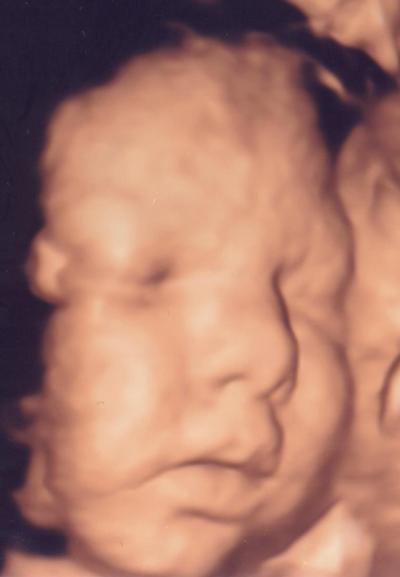

ich war heute mal wieder bei meiner Feindiagnoseärztin. Hugo gehts gut soweit. Zwar haben sie noch irgendwas mit einer aorta am hezren festgestellt, aber das ist nicht weiter dramatisch. ist wohl normal bei kindern mit herzfehlern. er wiegt jetzt jedenfalls 2170 gramm und ist ca. 41 cm groß. bild im anhang....endlich mal hat er keine hände vorm gesicht...und diesmal kommt er eher nach mir, als nach seinem vater...

Bild zu Bericht pränatale Diagnostik - Forum für August - Mamis

Wie schön das Bild! Der sieht ja echt knuffig aus!

Süss die nase :-) schön das es nix weiter schlimmeres es. Puuuuu Wie immer von toni grüsse an hugo